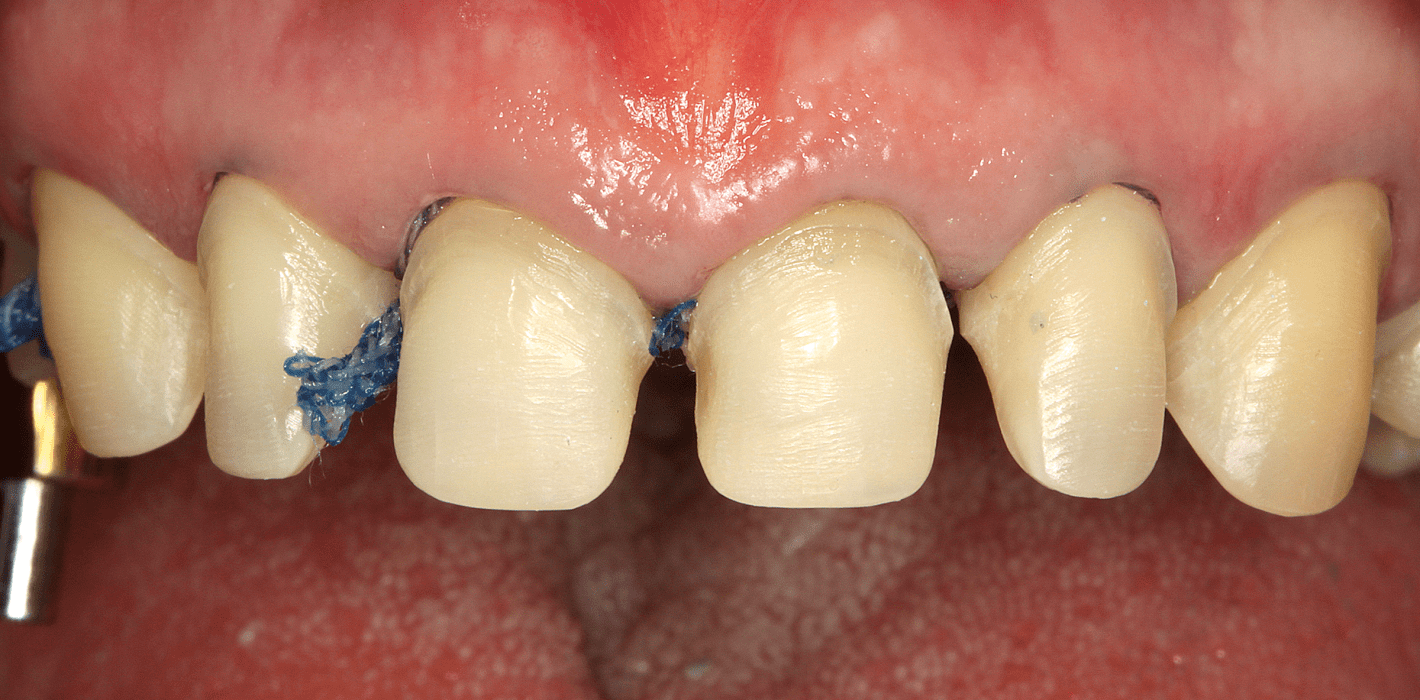

- Präparation im Bereich 13-23 zur Aufnahme von Presskeramikfullveneers (Hohlkehldiamant 886-012 M, Öko Dent und Finierer FG 8878/014, Komet; Abb. 12).

- Zweifache Abdrucknahme der präparierten Zähne mittels Doppelfadentechnik: Einbringen eines ersten, getränkten (Racestyptine solution, Septodont) Fadens (Ultrapak 0, Ultradent), über welchen ein zweiter getränkter Faden größeren Durchmessers gelegt wird (Ultrapak 1, Ultradent). Ca. zehn Minuten Wartezeit bis zur Abdrucknahme mit den gelegten Fäden.

- Die Abdrucknahme erfolgt nach Entfernung des zuletzt gelegten Fadens (der zuerst gelegte Faden geringeren Durchmessers verbleibt im Sulkus) mittels eines A-Silikons in Doppelmischtechnik einzeitig: Umspritzung der präparierten Zähne mit dünnfließendem Material (Express Ultra-Light Body, 3M Espe) und Einbringen des schwerfließenden Materials, (Express Penta Putty, 3M Espe) in einen Abdrucklöffel (Rim Lock, DeTrey; Abb.13).